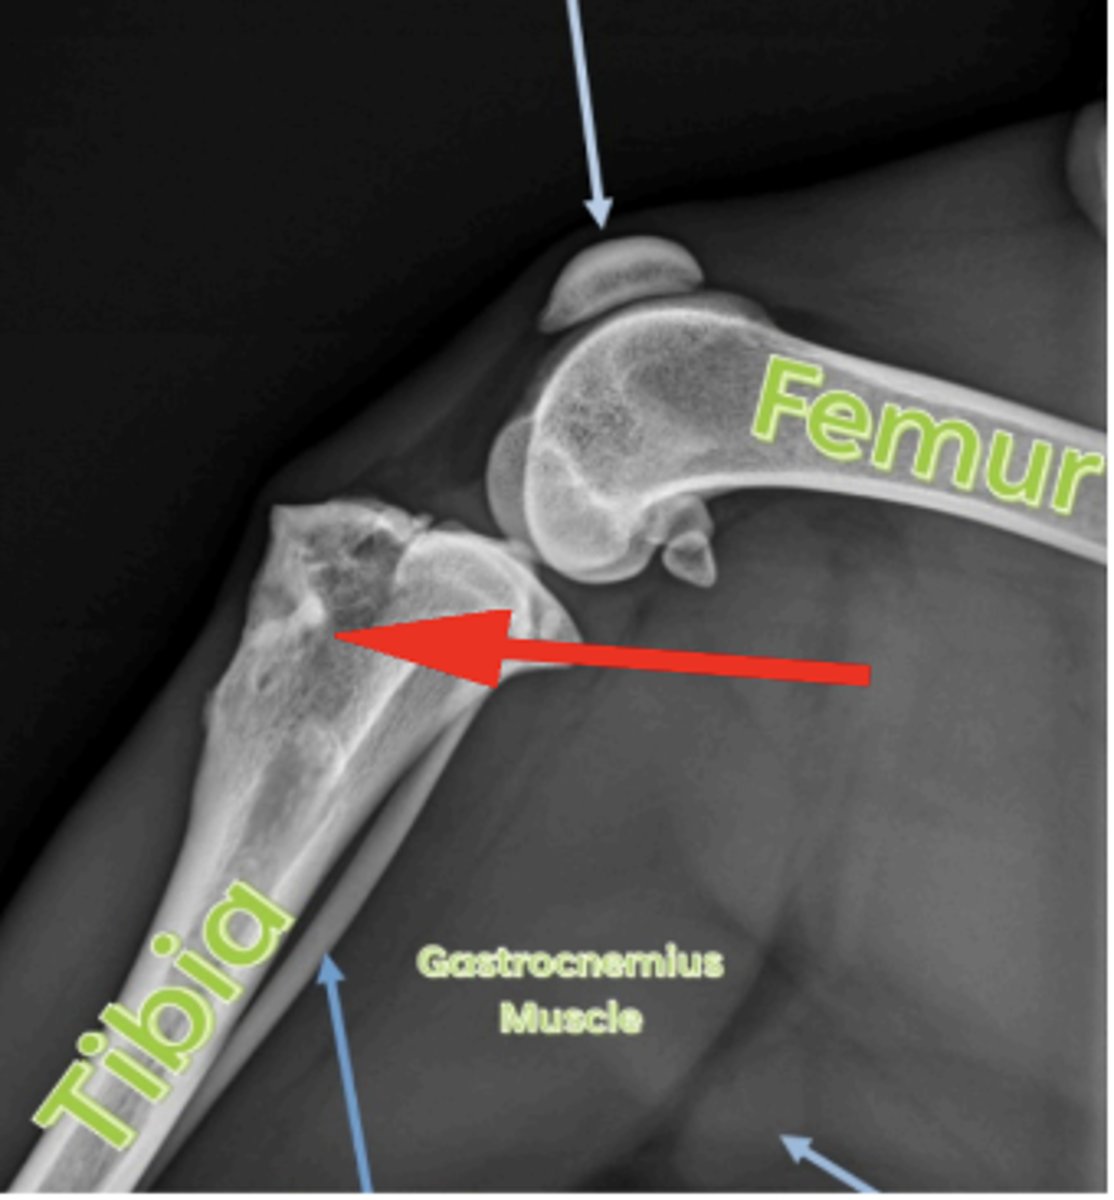

Tibial tuberosity

What anatomical location is indicated by the arrow?

OCD in distal tibia/intermediate ridge

2 yo horse w talocrural joint effusion; left hock lesion